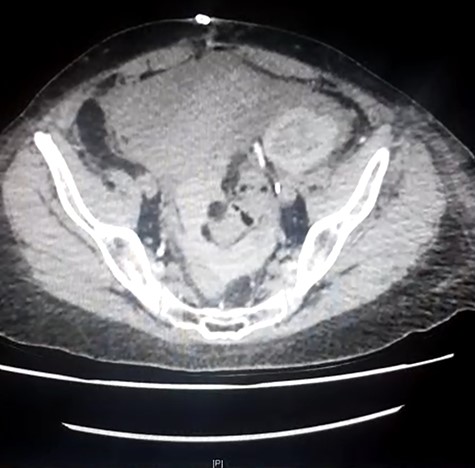

Repeat CT imaging with IV contrast at the referring hospital prior to transfer revealed large volume free fluid intraperitoneally with ongoing dilatation of the renal collecting system which was contrast filled. The distal ureter was not seen entering the bladder. The free fluid in the pelvis also demonstrated increased density raising concern for haematoma or possibly intravenous contrast (Figs 2 and 3).